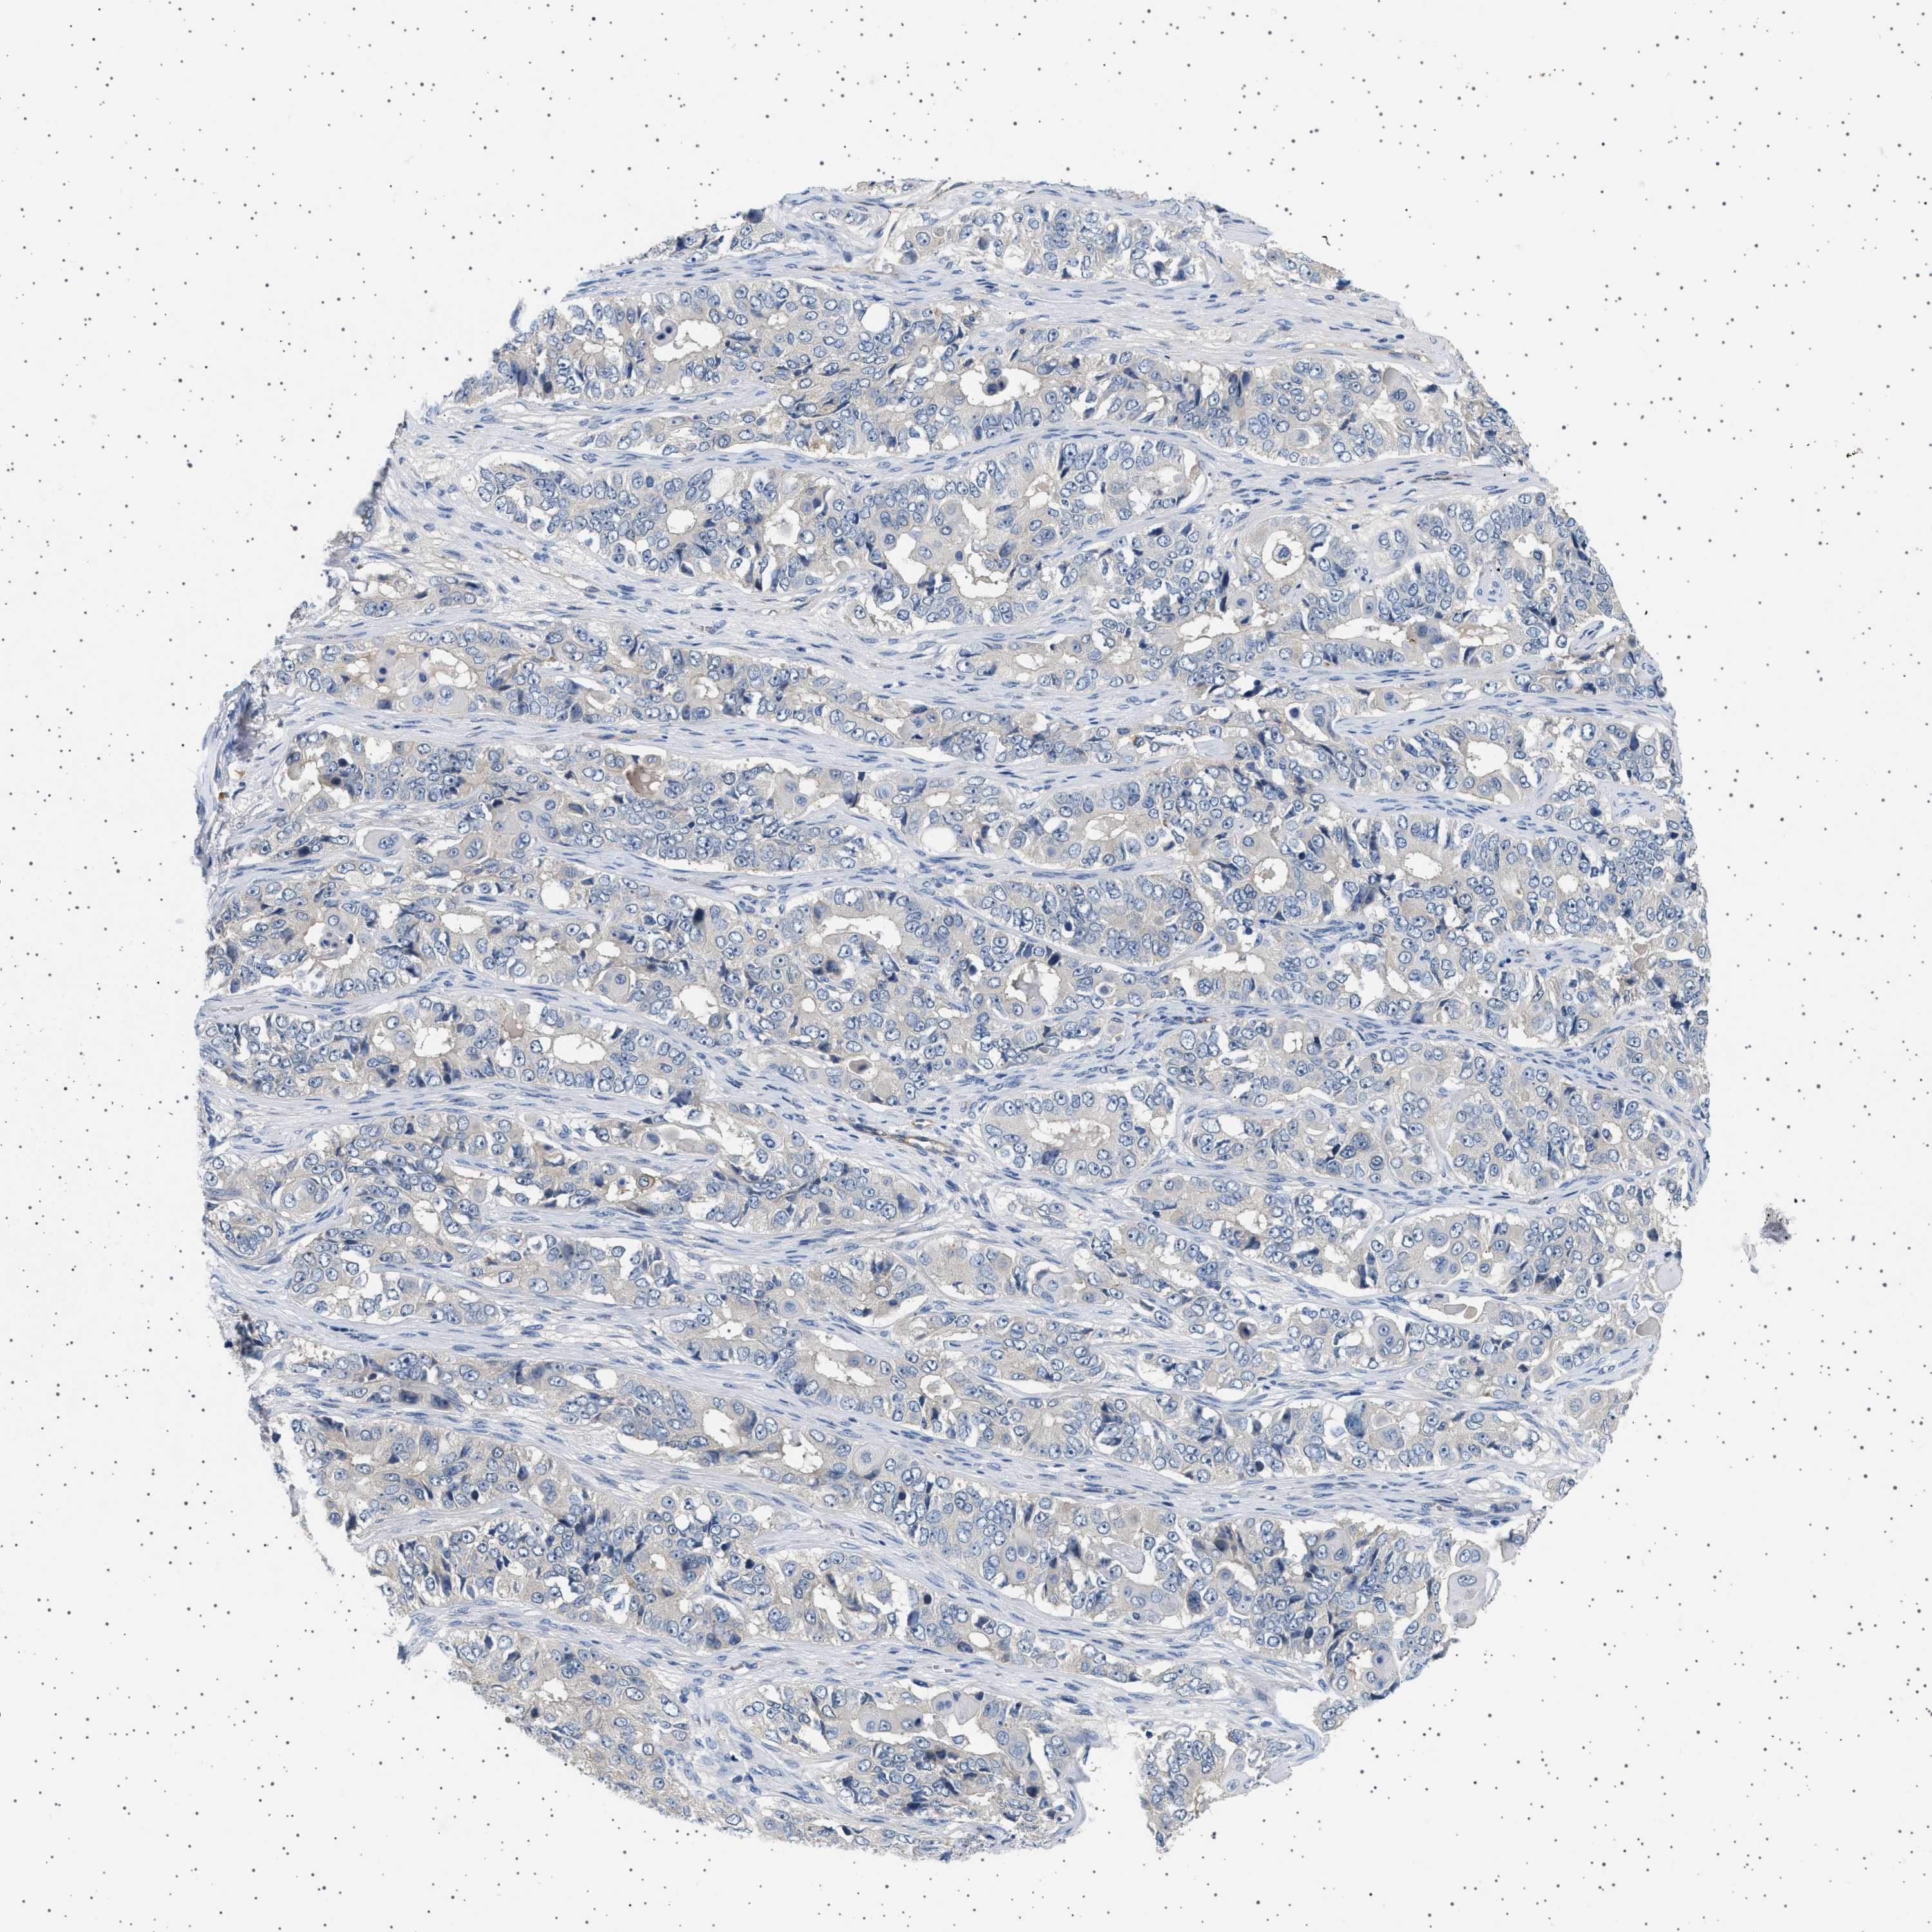

OVARIAN CANCER - Protein expressioni

A mouse-over function shows sample information and annotation data. Click on an image to view it in a full screen mode. Samples can be filtered based on level of antibody staining by selecting one or several of the following categories: high, medium, low and not detected. The assay and annotation is described here.

Note that samples used for immunohistochemistry by the Human Protein Atlas do not correspond to samples in the TCGA dataset.

Antibody stainingi

Antibody staining in the annotated cell types in the current human tissue is reported as not detected, low, medium, or high, based on conventional immunohistochemistry profiling in selected tissues. This score is based on the combination of the staining intensity and fraction of stained cells.

Each image is clickable and will lead to virtual microscopy that enables deeper exploration of all samples and also displays staining intensity scores, fraction scores and subcellular localization as well as patient and tissue information for each sample.

Antibody HPA018096

Carcinoma, endometroid